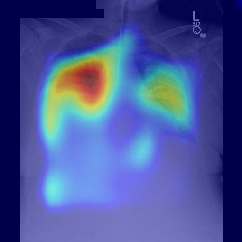

Fig.Β 5: Examples of class activation maps of positive cases. Left to right: image with annotation in blue, no L1 regularization, with L1 regularization, baseline.

Fig. 5 shows examples of class activation maps of positive cases for visual comparisons among the final models. These were produced using the Grad-CAM approach [14]. The images were annotated by an expert for the regions of opacity. Although all models correctly classified the cases as positives, the activation maps of the baseline model were barely correlated with the annotated regions, with more irrelevant hot spots outside the lungs. On the other hand, the activation maps of the models with feature selections were better correlated with the annotation. In other words, these smaller networks seems to be also more focused on the correct regions, which is a step towards explainability. The image in the third row shows that the VGG16 activation map has important components outside the lungs, focusing on English characters on the image. Whereas the reduced networks show more activation in marked areas of the lungs.